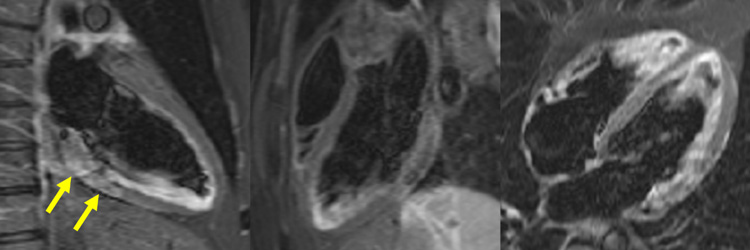

Figure 4A : Séquence de rehaussement tardif - Coupes petit-axe

Figure 4B : Séquence de rehaussement tardif - Coupes long-axe 2 cavités, 3 cavités et 4 cavités

Figure 4B : Séquence de rehaussement tardif - Coupes long-axes

Présence d’une zone de rehaussement tardif sous-épicardique aux niveaux inféro-latéro-basal et inféro-basal (zones blanches, flèches jaunes) comparée au reste du myocarde (noir).

Retenez le dogme selon lequel le muscle cardiaque sain apparaît toujours « noir » sur les séquences de rehaussement tardif.

Synthèse : faire le diagnostic étiologique de myocardite, infarctus ou syndrome de Tako-tsubo selon la topographie du rehaussement tardif

Visualisation d’un rehaussement myocardique systolique à prédominance sous-épicardique sur les cinés long-axe (2 cavités et 3 cavités) acquises après injection de gadolinium. C’est un signe assez évocateur d’œdème myocardique, qui est souvent retrouvé en cas de myocardite aiguë.

Myopéricardite aiguë est le diagnostic final à retenir devant une clinique compatible et une confirmation de l’atteinte de myocardite sur les arguments d’IRM cardiaque avec co-localisation parfaite de la zone de rehaussement tardif sous-épicardique (séquences de rehaussement tardif), de l’œdème myocardique sous-épicardique (séquences T2-mapping et T2-STIR) et d’un rehaussement myocardique systolique à prédominance sous-épicardique sur les cinés IRM aux niveaux inféro-latéro-basal et inféro-basal.